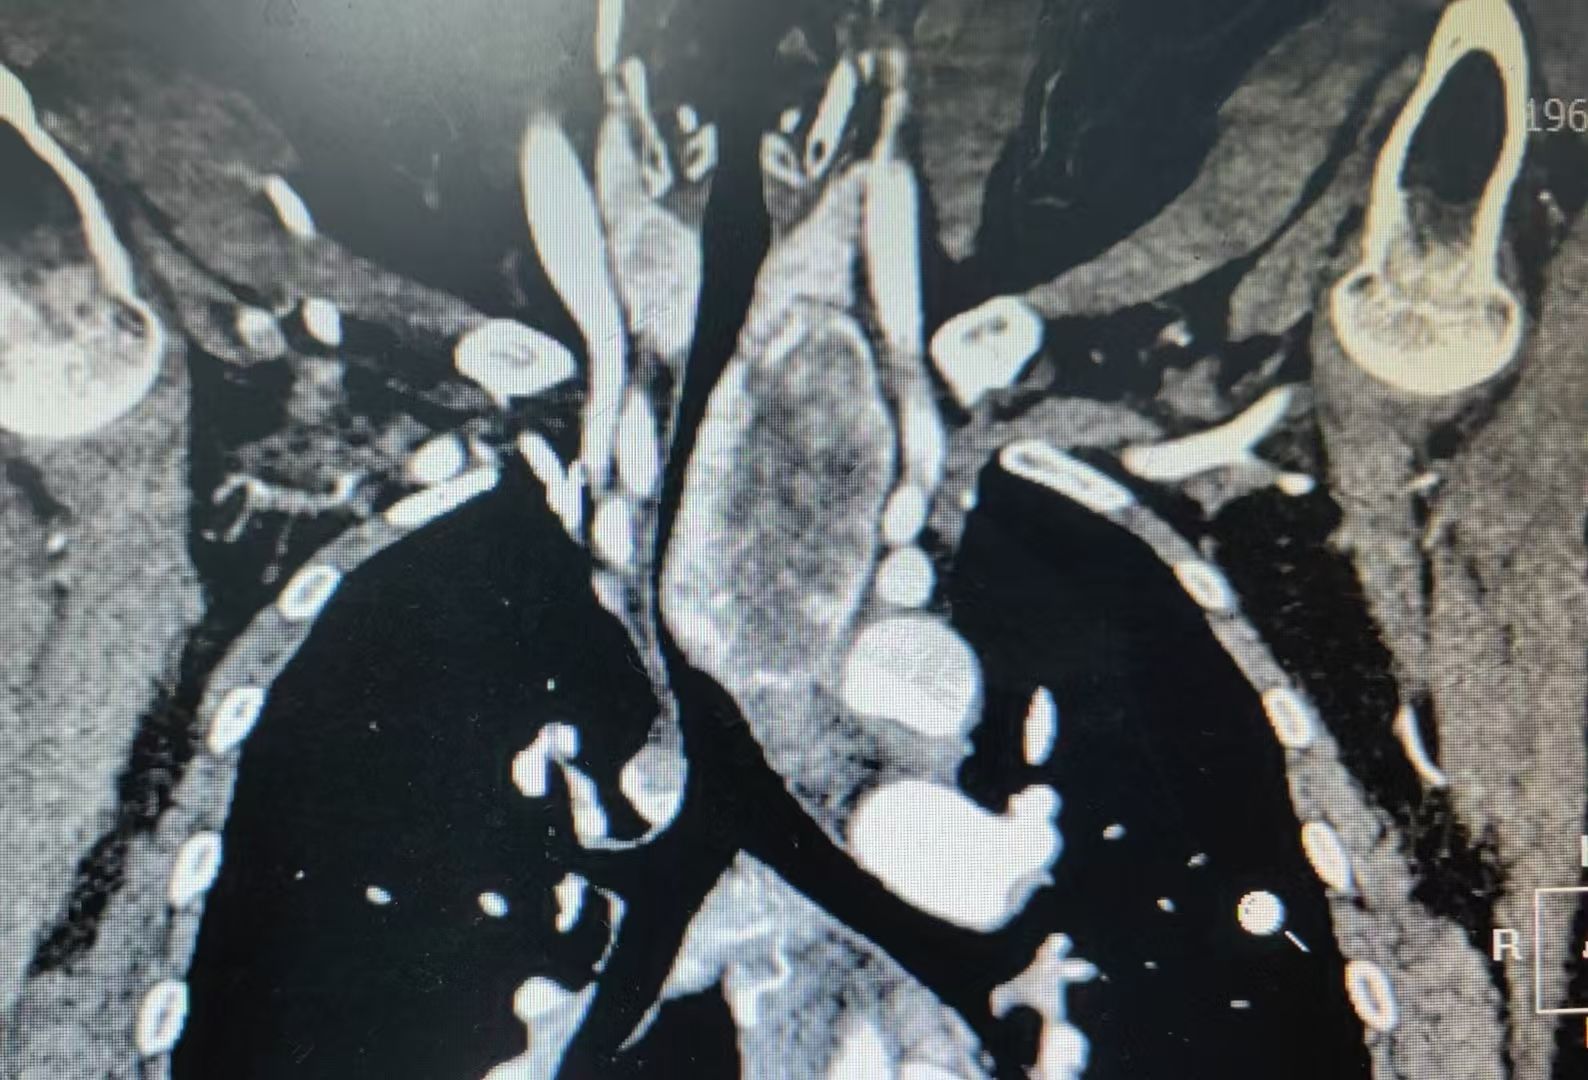

患者3 年前体检发现纵隔肿瘤,近期复查显示,上纵隔、甲状腺左侧叶后下方有一约 78mm×49mm×44mm 的团块状异常强化病灶,邻近气管、食管及主动脉弓分支受压移位,手术空间狭小且周围血管神经丰富,稍有不慎便可能造成严重并发症,对手术团队的技术和心理素质都是极大考验。

面对复杂病情,胸外科团队多次组织病例讨论。经全面评估患者病情,团队精准判断,选择经正中入路胸骨劈开的手术方式。该入路能为术者提供宽阔、直接的手术视野,便于在复杂的纵隔结构中精准操作,术中也证实此入路为该患者最恰当的手术方式。

术中,肿瘤与气管、食管及头臂干动脉毗邻,操作时需万分谨慎。姜建涛主任凭借丰富的经验和娴熟的技巧,成功地分离肿瘤与周围血管、神经等组织;团队成员马跃峰副主任医师、孙良璋主治医师、郭询医师分工明确、配合默契,及时提供术野暴露等支持;麻醉医生精准调控麻醉深度,确保患者生命体征平稳。在团队的紧密协作下,最终成功完整切除纵隔肿物,术中出血少,未出现并发症。